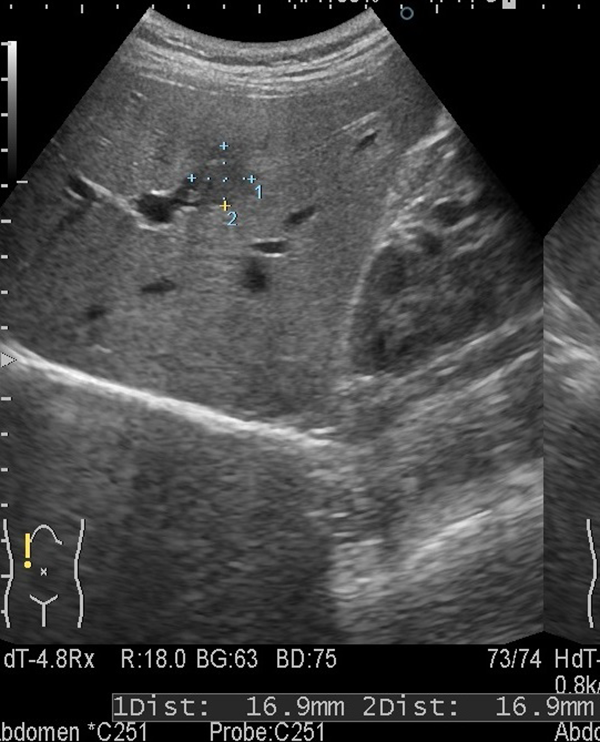

①肝内胆管癌

1. 肝臓の中央やや上寄りに周囲より黒っぽい不整な領域を認めます。

3. この時点で径16.9×16.9mmでありステージI期と考えられます。

このサイズで胆管癌が見つかることは非常にまれです。